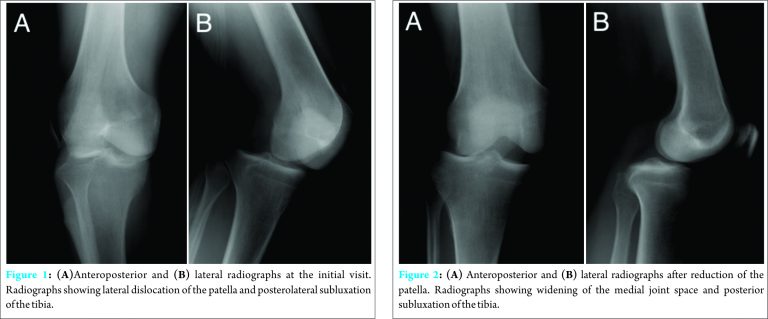

A 33-year-old man presented to the emergency department of our hospital with a twisting injury to his right knee and an open fracture of the left lower thigh that occurred while he was operating a rotary snow removal vehicle and his left lower thigh became trapped in the rotary blade. Physical examination revealed that the right knee joint was fixed at 30° flexion with a lateral shift of the patella. The contralateral open fracture was classified as grade 3A using the Gustilo–Anderson classifications ystem. No neurovascular injury to either leg was detected. Radiographic evaluation confirmed lateral dislocation of the patella and posterolateral subluxation of the knee (Fig. 1).

On the day of injury, the open fracture of the left lower thigh was stabilized with an external fixator after debridement and the dislocated patella of the right knee was reduced. However, closed reduction for knee joint dislocation could not be performed successfully. Plain radiographs after manipulation showed widening of the medial joint space and tibial posterolateral displacement (Fig. 2). The characteristic dimple sign was observed over the medial joint line (Fig. 3). On the medial aspect of the injured knee, the medial femoral condyle was palpable just beneath the skin. Two days after the injury, closed reduction was attempted under general anesthesia. The knee was flexed to 120° and valgus stress and internal rotation of the lower thigh were applied. The dislocated knee was reduced and the dimple sign disappeared. The posterolateral dislocation could be reproduced by external rotation at 100–120° flexion. After reduction, ligament instability tests were positive for valgus stress, with signs of posterior sagging in the posterior drawer test, and negative for the Lachman test, pivot shift test, extension recurvatum test, and dial test. A subsequent arthroscopic examination also revealed a complete midsubstance tear of the posterior cruciate ligament (PCL) (Fig. 4A) and a partial tear of the posterolateral bundle of the anterior cruciate ligament (ACL), which were not reconstructed (Fig. 4B). A peripheral longitudinal tear of the lateral meniscus was repaired using the Fast Fix 360 Meniscal Repair System (Smith & Nephew, Andover, MA, USA) (Fig. 4C).